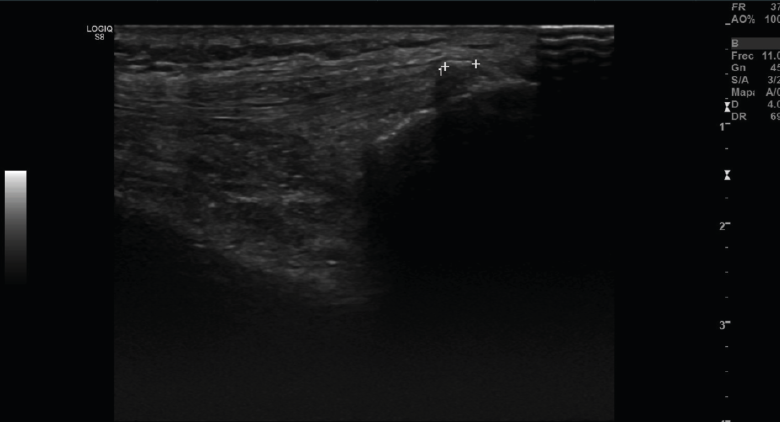

Tanto el ligamento lateral interno (LLI) como el ligamento lateral externo (LLE) pueden ser valorados por ecografía (Figura 7).

Figura 7. Corte coronal de una ecografía de rodilla. A: engrosamiento del ligamento lateral externo en la inserción proximal por un esguince de grado I; B: engrosamiento del ligamento lateral interno.